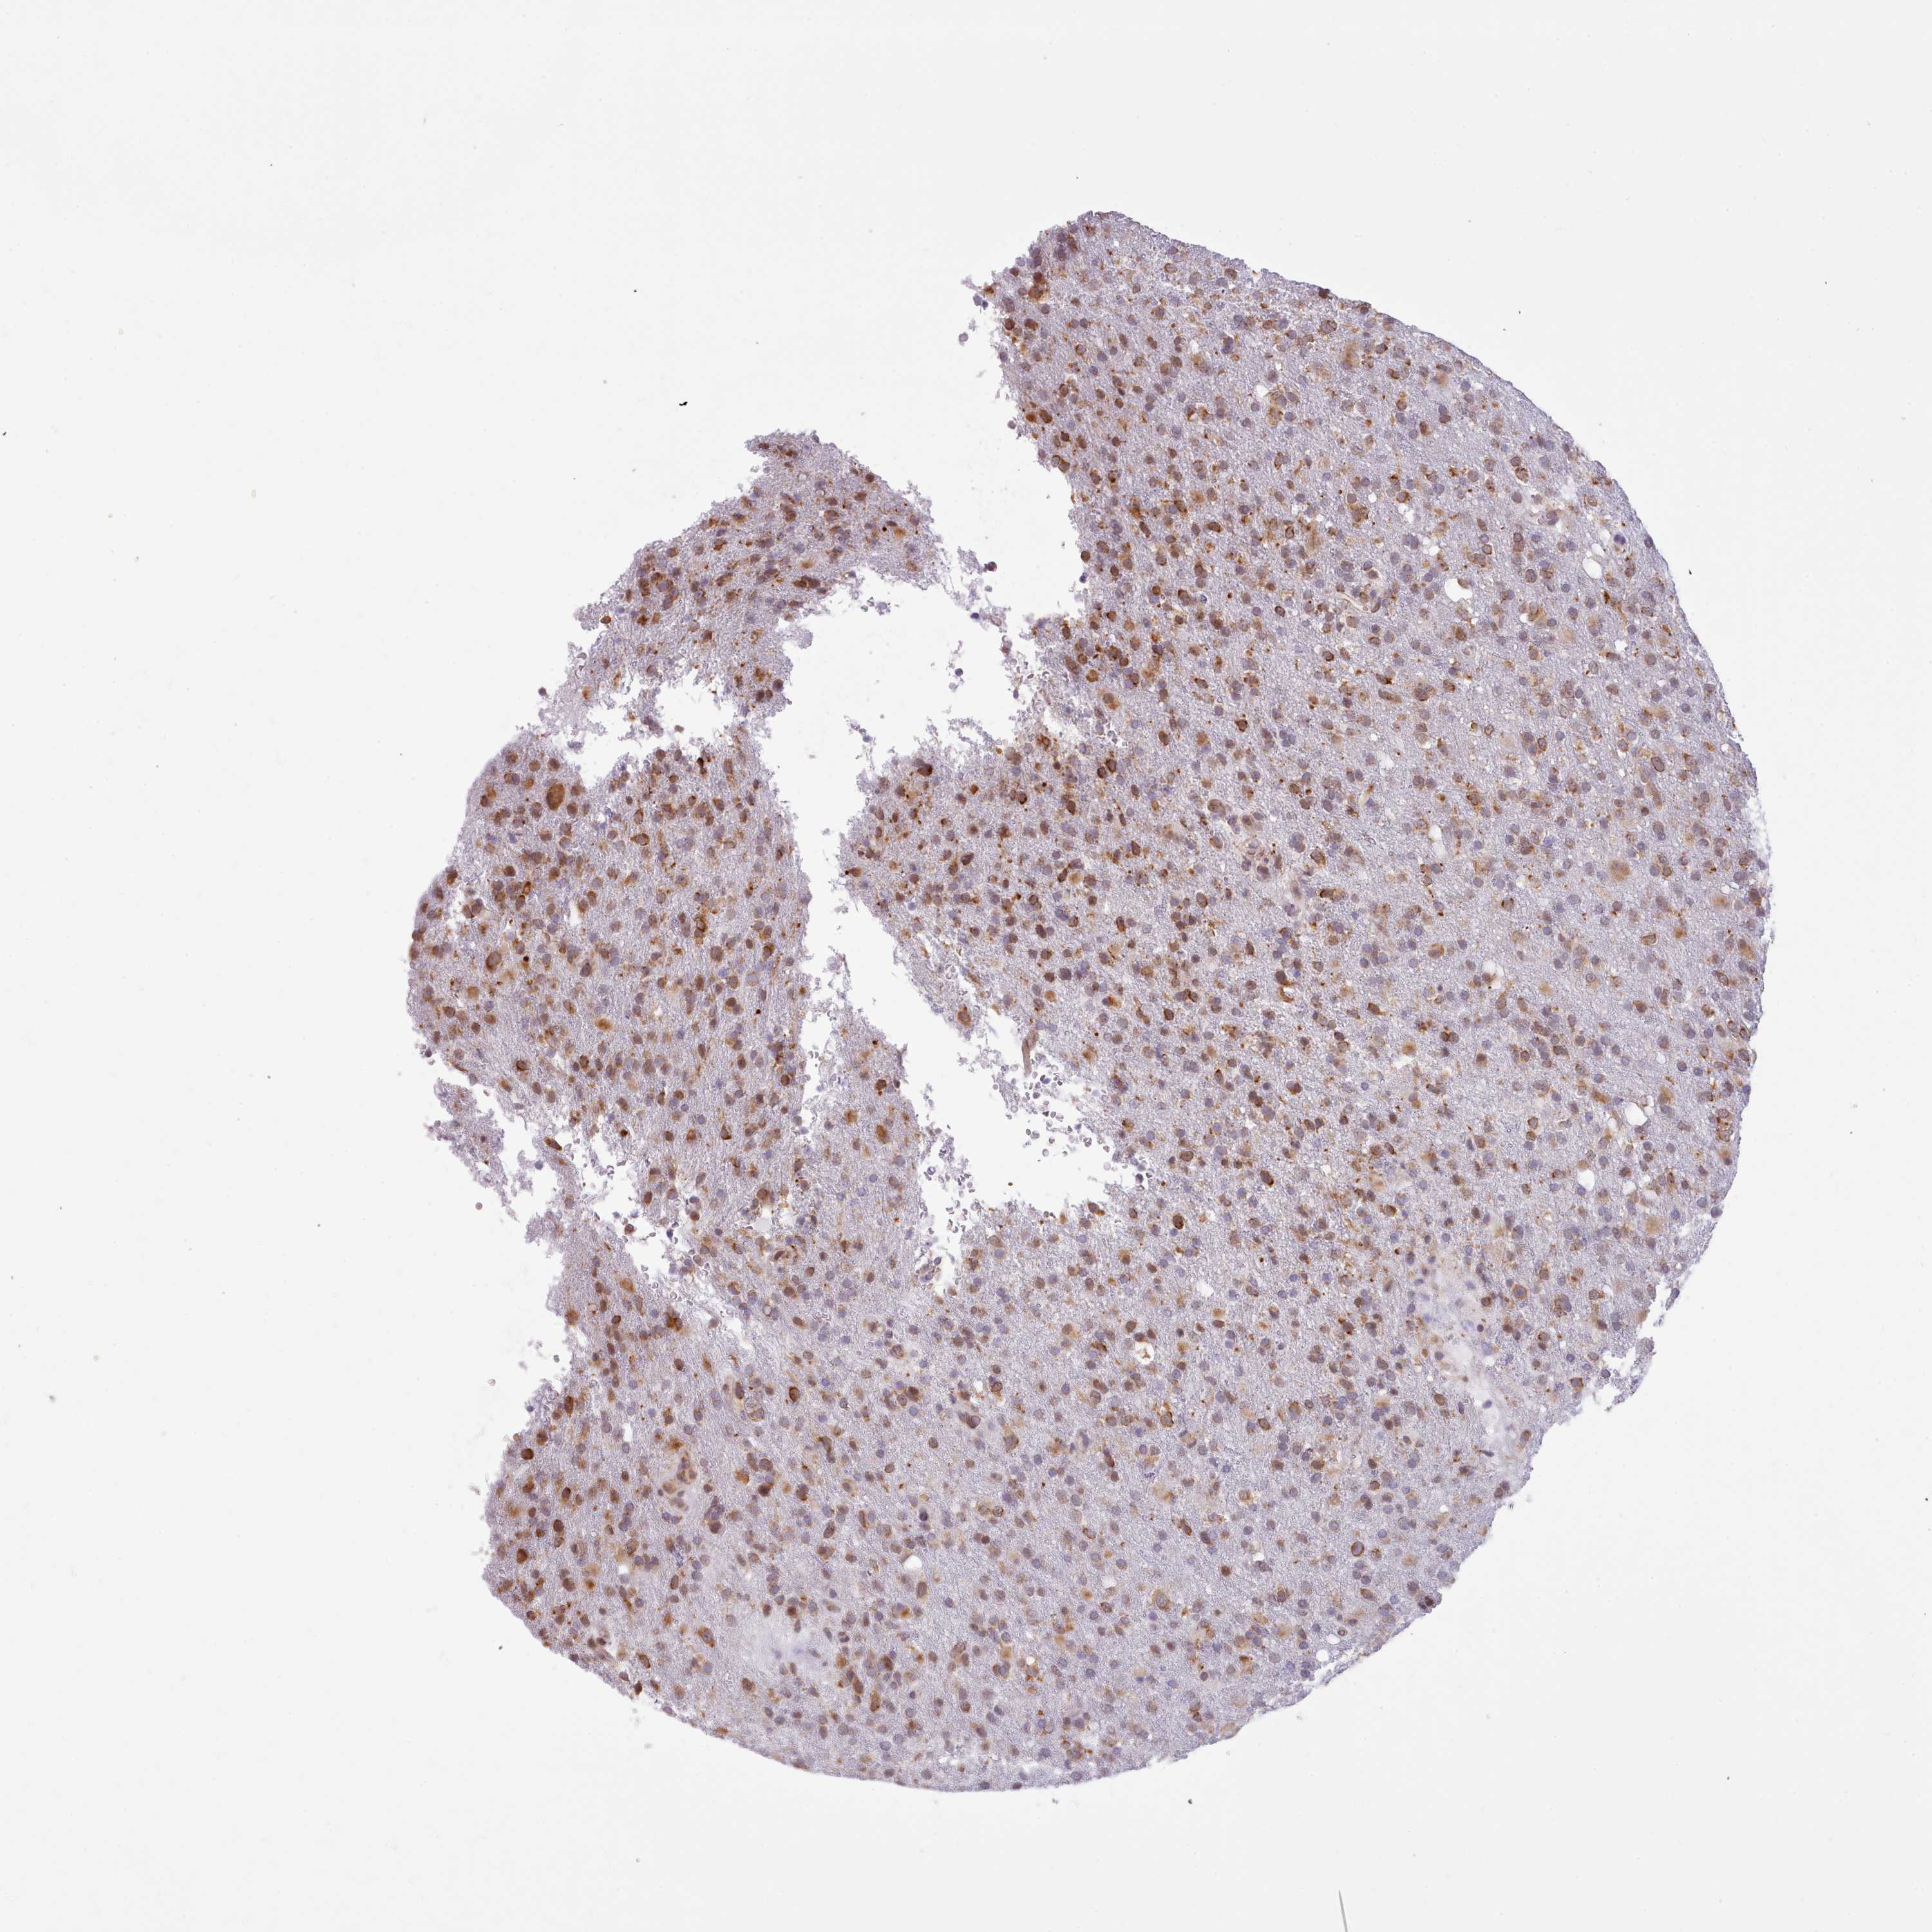

GLIOMA - Protein expressioni

A mouse-over function shows sample information and annotation data. Click on an image to view it in a full screen mode. Samples can be filtered based on level of antibody staining by selecting one or several of the following categories: high, medium, low and not detected. The assay and annotation is described here.

Note that samples used for immunohistochemistry by the Human Protein Atlas do not correspond to samples in the TCGA dataset.

Antibody stainingi

Antibody staining in the annotated cell types in the current human tissue is reported as not detected, low, medium, or high, based on conventional immunohistochemistry profiling in selected tissues. This score is based on the combination of the staining intensity and fraction of stained cells.

Each image is clickable and will lead to virtual microscopy that enables deeper exploration of all samples and also displays staining intensity scores, fraction scores and subcellular localization as well as patient and tissue information for each sample.

Antibody HPA049407

Staining

High

Medium

Low

Not detected

Intensity

Strong

Moderate

Weak

Negative

Quantity

>75%

75%-25%

<25%

None

Location

Nuclear

Cytoplasmic/membranous

Cytoplasmic/membranous,nuclear

Glioma, malignant, High grade

Glioma, malignant, Low grade